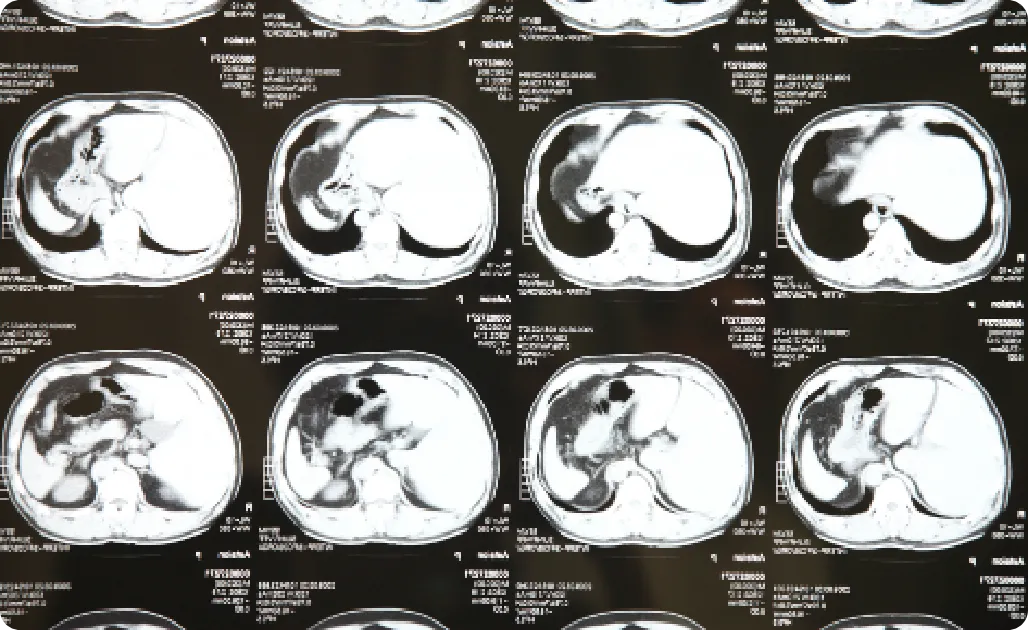

MRI検査室

脳出血や脳腫瘍との鑑別も

可能なCT完備

頭痛の中には、命に関わる脳出血や脳腫瘍が原因となっているケースもあります。

当院では当日の頭部CT検査が可能なため、緊急性の高い疾患との鑑別も迅速に対応いたします。

レントゲン写真

このような重大な病気を見逃さないためにも、当院では症状に応じて

CT検査を即日実施し、必要に応じてMRI検査や神経内科との連携も行います。

Q. 脳の病気が心配です。調べてもらえますか?

A. はい。当院では頭部CT検査が当日可能です。必要に応じて連携病院にてMRI等も実施いたします。